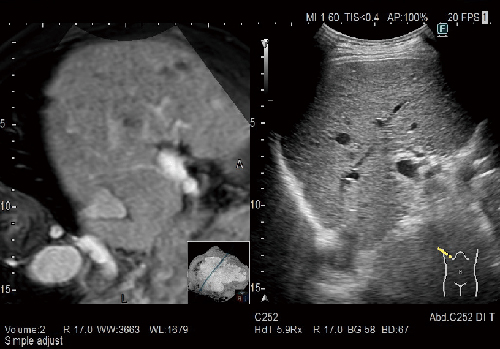

「Real-time Virtual Sonography(RVS)」搭載(オプション)

CT・MRI・超音波診断装置のボリュームデータから作成したMPR 画像を超音波画像とリアルタイムで同期させる機能です。治療をサポートする機能であるRVSは治療の位置決めを補助したり,超音波検査だけでは見つけづらい小さな病変の発見をサポートします。